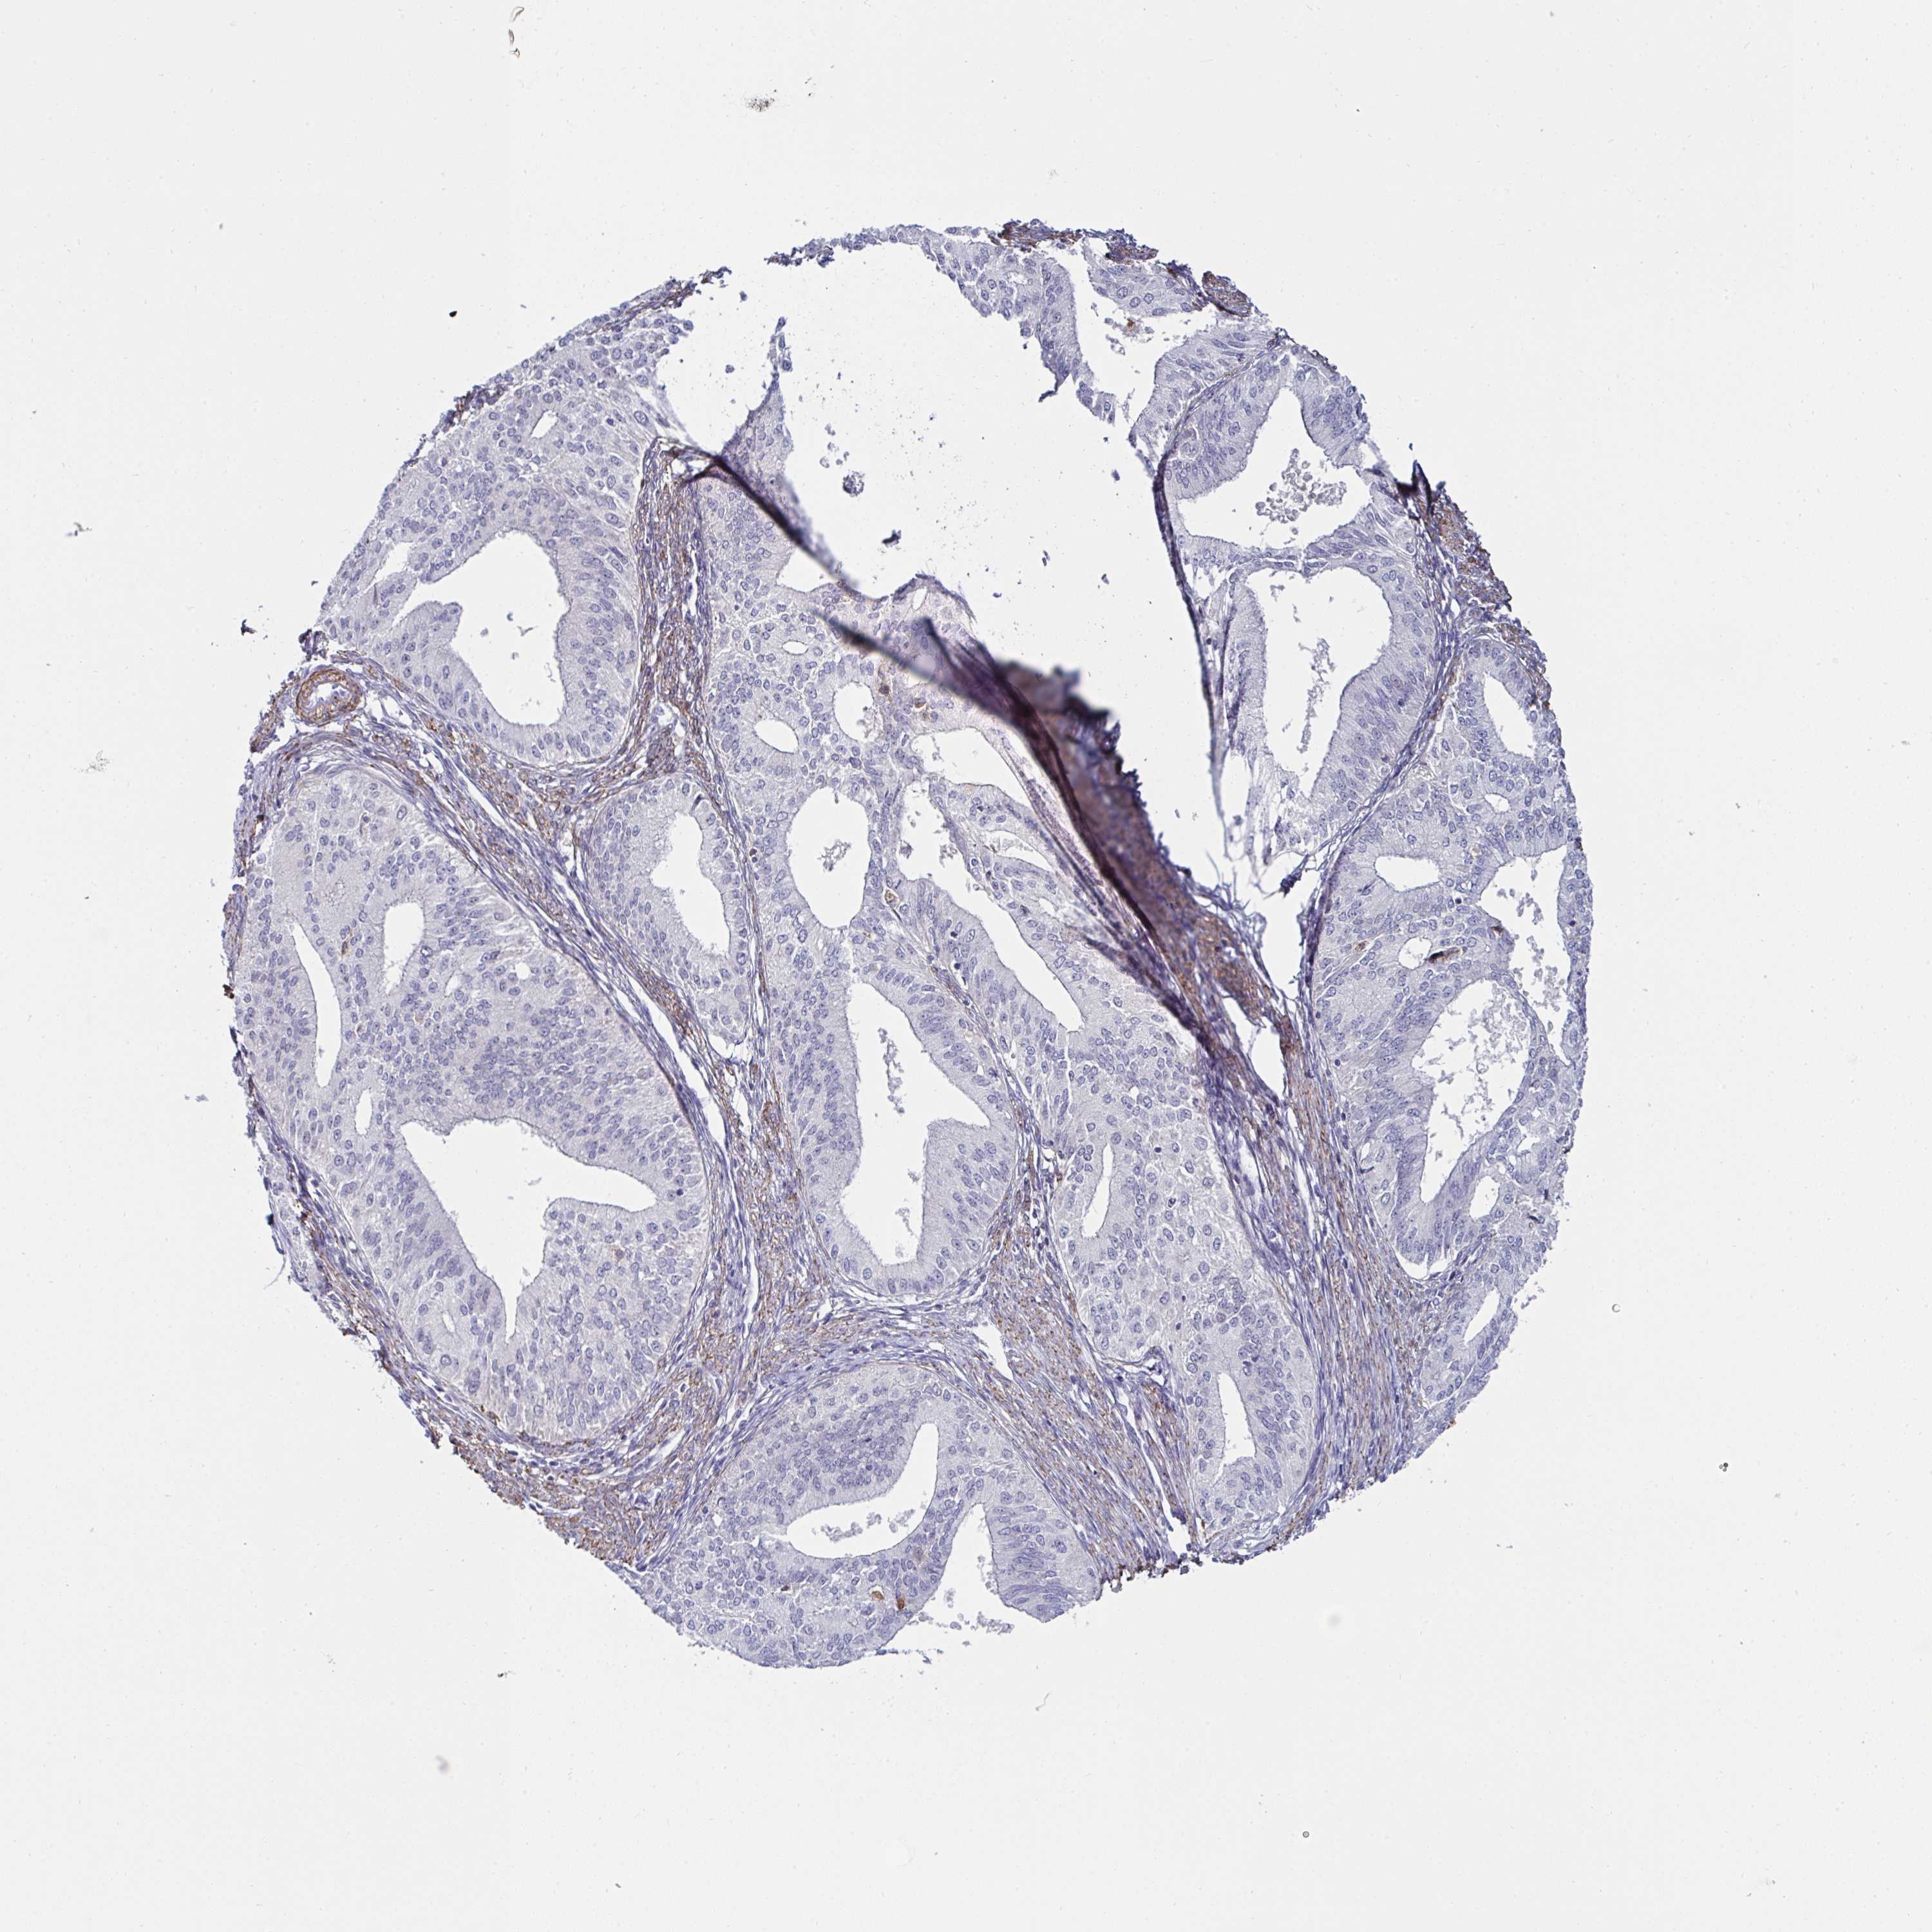

ENDOMETRIAL CANCER - Protein expressioni

A mouse-over function shows sample information and annotation data. Click on an image to view it in a full screen mode. Samples can be filtered based on level of antibody staining by selecting one or several of the following categories: high, medium, low and not detected. The assay and annotation is described here.

Note that samples used for immunohistochemistry by the Human Protein Atlas do not correspond to samples in the TCGA dataset.

Antibody stainingi

Antibody staining in the annotated cell types in the current human tissue is reported as not detected, low, medium, or high, based on conventional immunohistochemistry profiling in selected tissues. This score is based on the combination of the staining intensity and fraction of stained cells.

Each image is clickable and will lead to virtual microscopy that enables deeper exploration of all samples and also displays staining intensity scores, fraction scores and subcellular localization as well as patient and tissue information for each sample.

Antibody HPA057232

Staining

High

Medium

Low

Not detected

Intensity

Strong

Moderate

Weak

Negative

Quantity

>75%

75%-25%

<25%

None

Location

Nuclear

Cytoplasmic/membranous

Cytoplasmic/membranous,nuclear

Adenocarcinoma, NOS